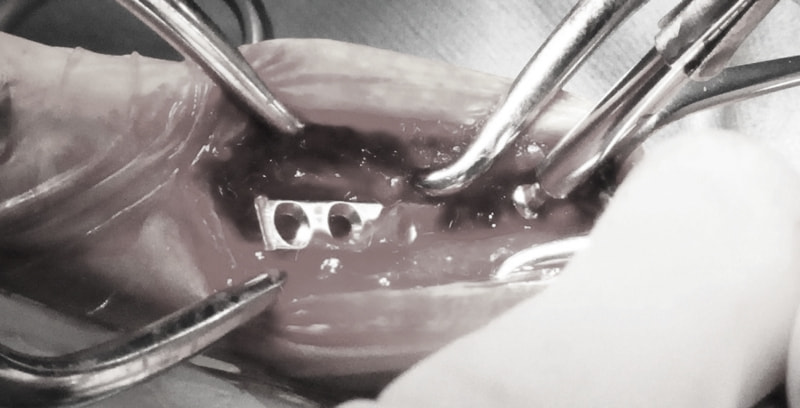

脊髄の減圧、脊柱管の再構築・安定化を目的に、片側椎弓切除術およびMatrixMANDIBLE Plateによる椎体固定を実施しました。

隣接椎体を架橋するようにプレートを設置しました。